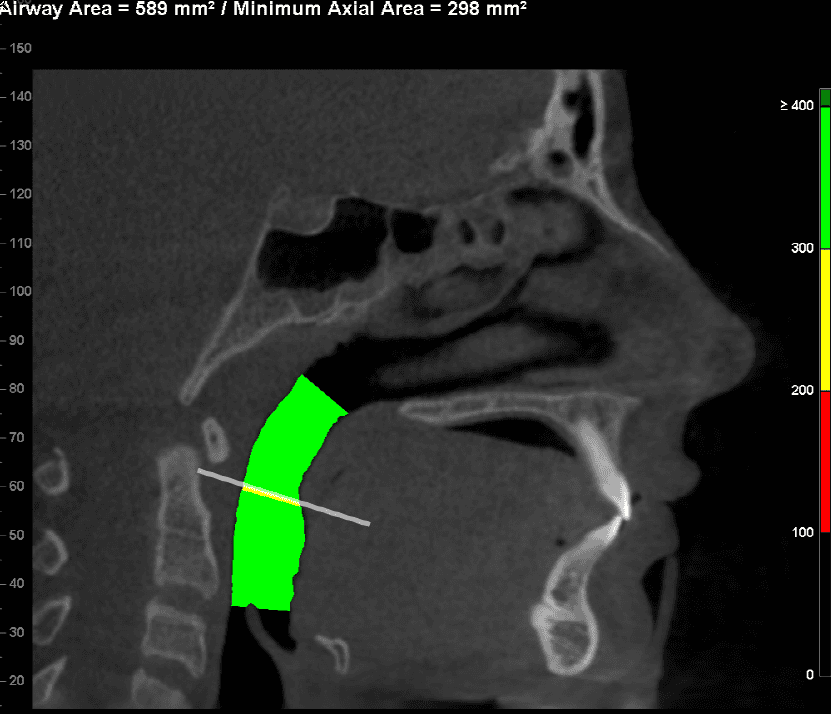

Why Airway Orthodontics

At Van Vliet & Ganz Orthodontics, we believe great orthodontic care goes beyond just straight teeth. Itโs about supporting proper function โ and that starts with how you breathe. Airway orthodontics focuses on identifying and addressing underlying issues that affect the size, shape, and function of the airway. The goal? To create space not just for teeth, but for better breathing, better sleep, and improved overall health.

This modern, holistic approach allows us to help patients-especially children-correct problems early, reduce the risk of future complications, and improve quality of life in ways that traditional orthodontics alone may not address.

For many patients, an orthodontic intervention in Highland, NY or Ramsey, NJ can improve and sometimes eliminate these risks. Below are pictures of an OSA patient that benefitted from orthodontic treatment’s life-changing effects at Van Vliet & Ganz Orthodontics.